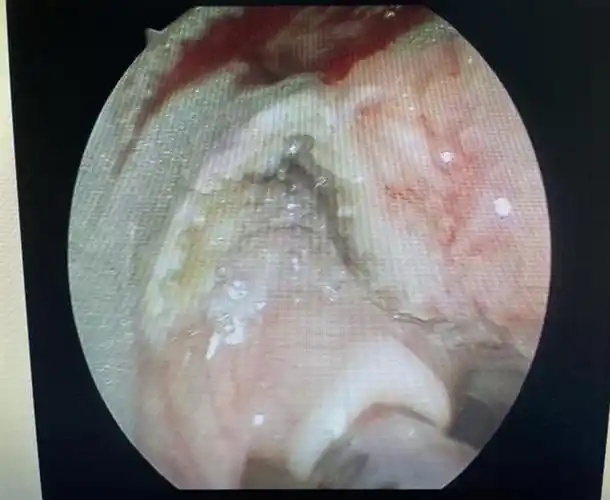

真如鲠在喉济一2个月小孩嗓子里长了巨大肿瘤